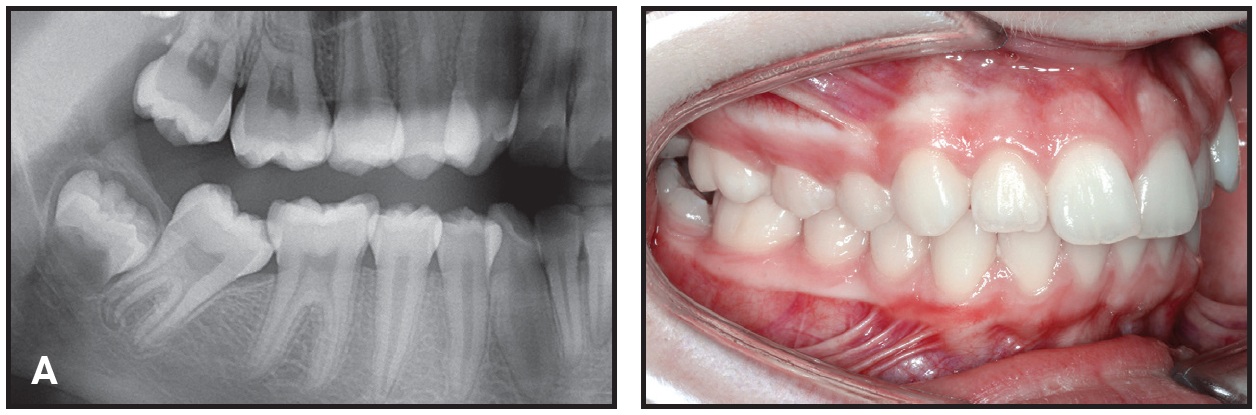

Mandibular second-molar impactions occur in 2-3% of orthodontic patients (A).1 An open-coil spring is commonly placed between the first- and second-molar tubes on a nickel titanium archwire to upright the second molar. Because of the limited access, however, it can be challenging to simultaneously thread an archwire and compress the open-coil spring. This Pearl avoids the issue by substituting a twin bracket for the first-molar tube.